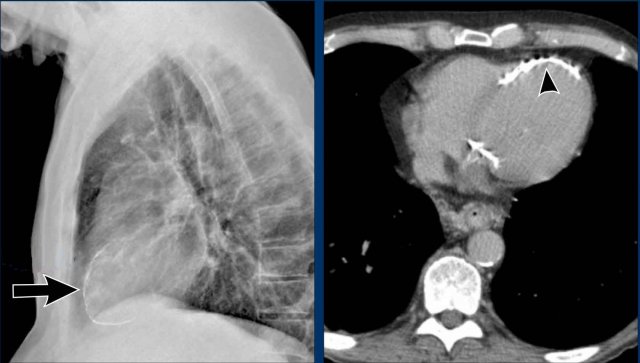

Case Example 1: Pericardial Effusion Mimicking Cardiomegaly

- On the chest radiograph, the patient appears to have a dilated heart.

- However, CT imaging clearly demonstrates that the apparent enlargement is due to significant pericardial fluid accumulation, not true myocardial chamber enlargement.

Postoperative Pericardial Hemorrhage

In patients with recent cardiac surgery, a sudden change in heart size on chest X-ray should raise suspicion for pericardial bleeding, which may be life-threatening.

Case Example 2:

- A postoperative patient showed a change in the cardiac silhouette.

- Echocardiography detected only a minimal pericardial effusion.

Case Example 2 - CT imaging

- CT imaging revealed a large posterior pericardial effusion compressing the left ventricle (blue arrow: effusion; red arrow: compressed, contrast-filled left ventricle).

- Surgical exploration confirmed a large posterior pericardial hematoma.

Note: Minimal anterior fluid on ultrasound may underestimate the true volume if the effusion is loculated posteriorly, highlighting the value of CT in postoperative cases.